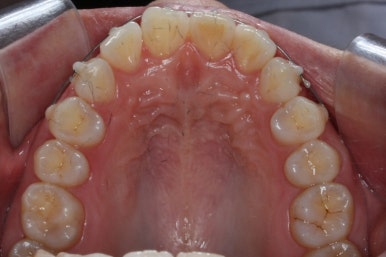

우여곡절 끝에 어찌어찌 마무리를 하게 되었습니다.

두 번째 교정에서 걸린 시간은 총 3개월이었습니다.

첫 번째 교정기간 4개월과 합하면 총 7개월이 걸렸는데 중간에 치아가 다시 삐뚤어지는 바람에 조금 많이 걸리긴 했습니다.

어쨌든, 앞니는 가지런하게 마무리가 잘 되었고, 앞니 안쪽에는 유지철사를 부착하고 치료를 종료하였습니다.

부산앞니교정 키다리아저씨치과에서 시행한 이번 MTA 부분교정의 전후 비교입니다.

위아래 앞니가 가지런해졌고, 작은 앞니의 얼룩무늬도 없어졌네요.